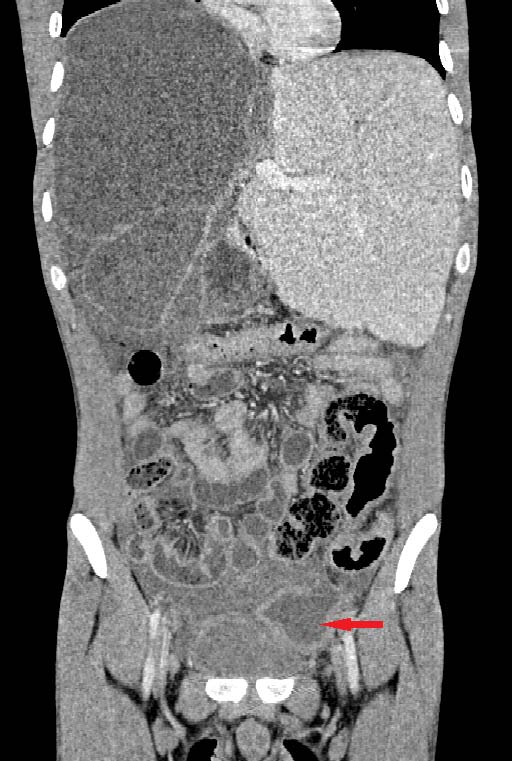

Une tomodensitométrie abdomino-pelvienne est réalisée sans et après injection de produit de contraste. Cette dernière, montre au niveau du foie droit Corresponding Author ?: Internat Hôpital Ibn Sina 40010 Rabat, Maroc. e-mail: [email protected] de multiples formations kystiques, à contenu liquidien pur ou cloisonné, bien circonscrites, confluentes, à paroi épaissie rehaussées en périphérie après injection de produit de contraste en rapport avec des kystes hydatiques hépatiques de taille et de type variable.

Il s'y associe également au niveau pelvien deux kystes hydatiques intra-péritonéaux, le premier est multi vésiculaire et le deuxième sus et latéro-vésicale gauche à paroi affaissée, discontinue associée à un épanchement péritonéal témoignant sa rupture dans la cavité péritonéale.

Le diagnostic de péritonite aigue généralisée par rupture d'un kyste hydatique intra-péritonéal associée à une hydatidose hépatique est retenu.